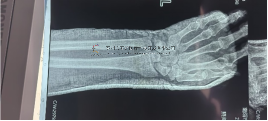

1.基本资料患者,男,46岁。主诉:外伤后右踝部疼痛、活动障碍13小时。2.术前检查踝关节CT扫描+三维重建:胫骨远端中度粉碎,骨折···

1.基本信息患者,女,75岁,主诉:踝部疼痛、肿胀,活动受限5天余。查体:右踝部畸形、肿胀明显,局部按压可触及异常活动及骨擦感···

术前影像术前影像术中透视术中透视术中透视术中透视安装外架术后外观及影像术后外观及影像术后外观及影像本文转载自好大夫平台:···